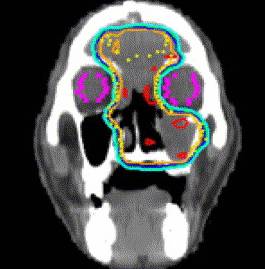

Methods and Materials: Between January 1987 and July 2005, 85 patients with PNS and nasal cavity cancer underwent postoperative RT. Most patients had squamous cell carcinoma (49%; n = 42), T4 tumors (52%; n = 36), and the maxillary sinus (53%; n = 45) as the primary disease site. The median radiation dose was 63 Gy. Of the 85 patients, 76 underwent CT simulation and 53 were treated with either three-dimensional conformal RT (27%; n = 23) or intensity-modulated RT (35%; n = 30). Acute and late toxicities were scored according to the Radiation Therapy Oncology Group radiation morbidity scoring criteria.

Results: With a median follow-up for surviving patients of 60 months, the 5-year estimates of local progression-free, regional progression-free, distant metastasis-free, disease-free, and overall survival rates were 62%, 87%, 82%, 55%, and 67%, respectively. On multivariate analysis, squamous cell histology and cribriform plate involvement predicted for an increased likelihood of local recurrence, and squamous cell histologic features predicted for worse overall survival. None of the patients who underwent CT simulation and were treated with modern techniques developed a Grade 3-4 late complication of the eye.